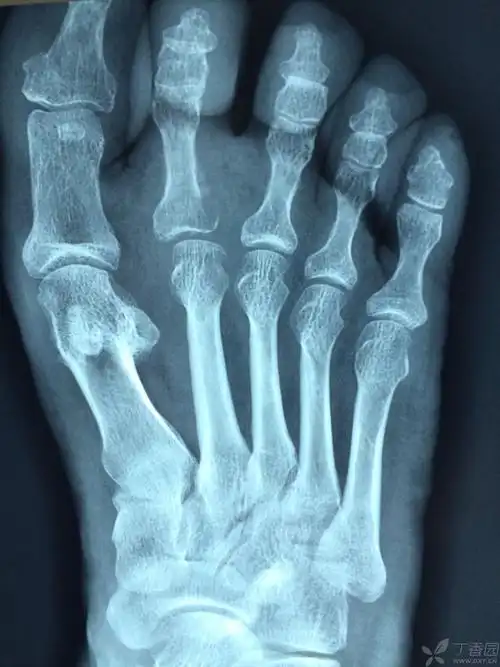

交通事故左足拇指近节趾骨骨折能凭上伤残吗?

苗大姐今年50岁,是一名左足第一趾骨近节骨折的患者.

左足第四趾近节趾骨头骨折,长时间依然没有完全复位,该如何治疗,恢复

拇趾近节趾骨粉碎骨折固定方式

近节趾骨proximalphalanx6.中节趾骨middlephalanx7.